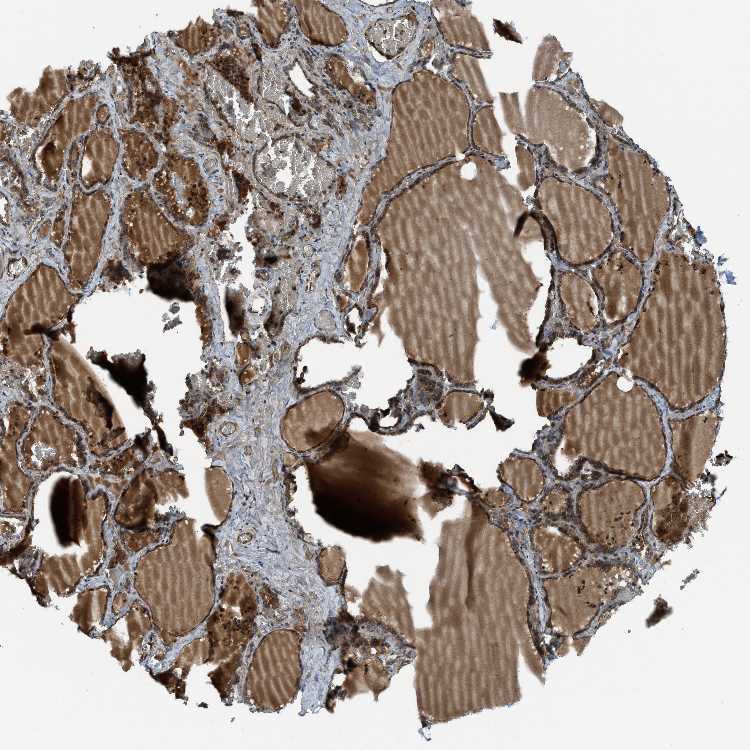

THYROID GLAND - Antibody stainingi

Antibody staining in the annotated cell types in the current human tissue is reported as not detected, low, medium, or high, based on conventional immunohistochemistry profiling in selected tissues. This score is based on the combination of the staining intensity and fraction of stained cells.

Each image is clickable and will lead to virtual microscopy that enables deeper exploration of all samples and also displays staining intensity scores, fraction scores and subcellular localization as well as patient and tissue information for each sample.

Antibody HPA025226Antibody CAB019296

Glandular cells MediumHigh